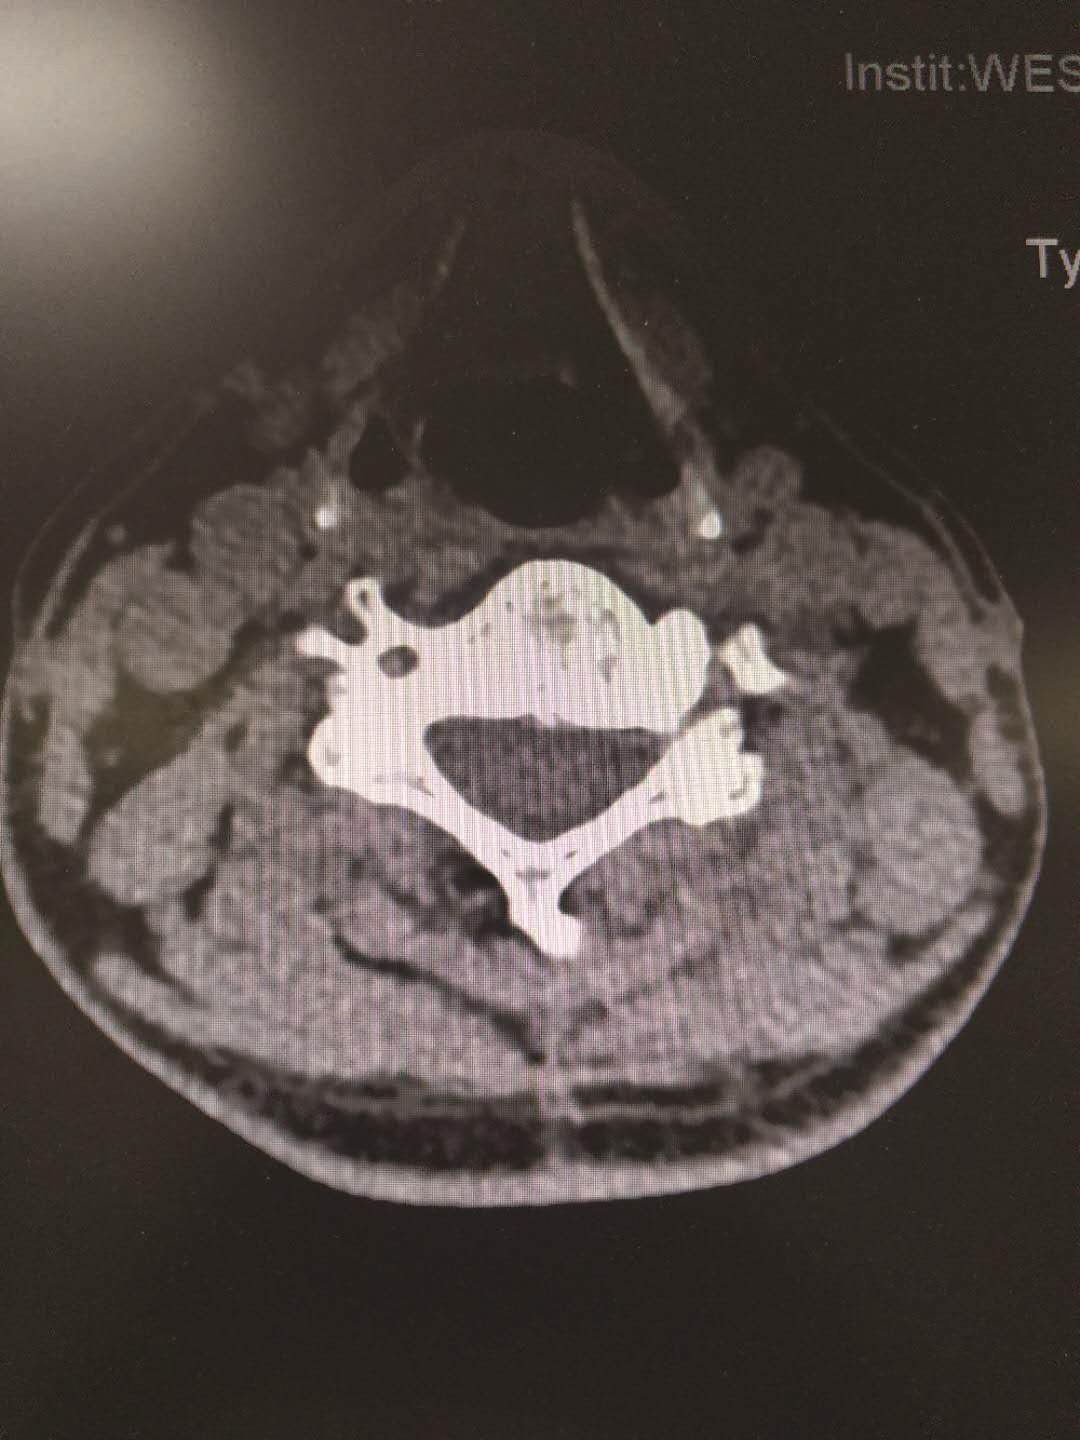

从横断面的角度显示颈椎的解剖及病理变化。